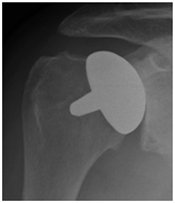

Shoulder replacement shoulder replacement

X-ray of shoulder showing a surface replacement